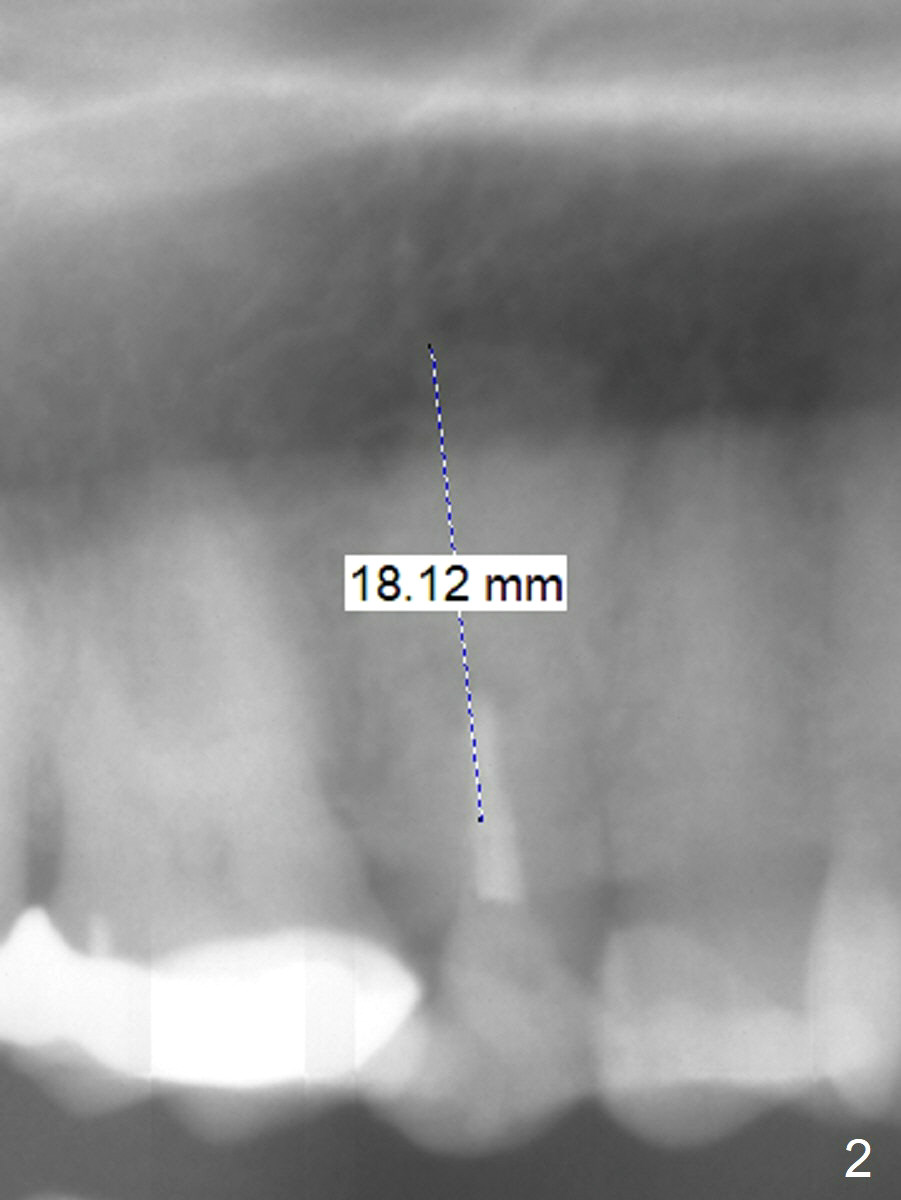

A 41-year-old woman has multiple restorations. One of them, the tooth #4, has palatally subgingival fracture. There is sufficient bone height (Fig.2,3). The apex seems to have ben resected with periapical radiopaque lesion (Fig.3 black *, possible synthetic or bovine bone). To get two point engagement into the native bone (red *), the longest bone-level implant will be placed.